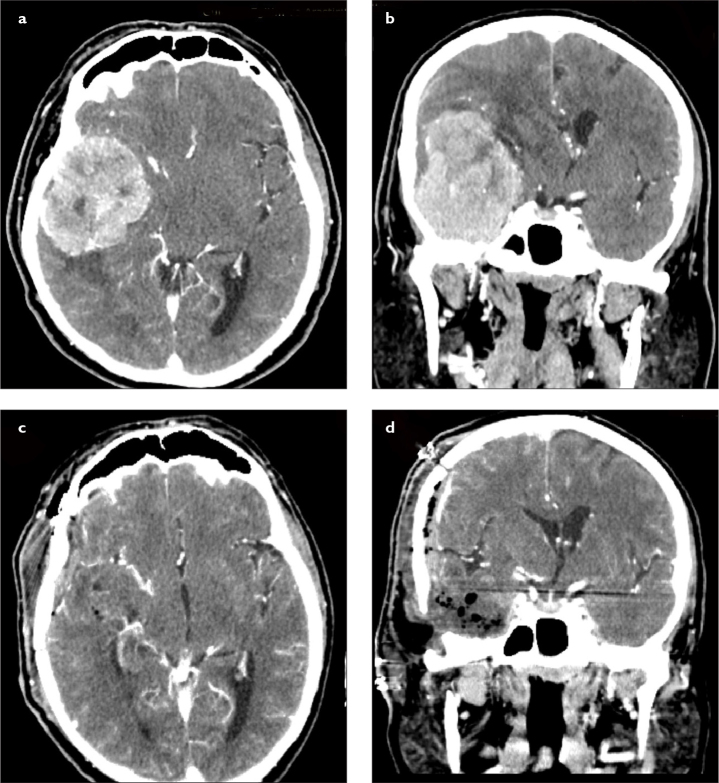

Objective: Giant intracranial meningiomas are a challenge for neurosurgeons because of their size and location in the cranium. Difficult tumor dissection and encasement of important neurovascular structures make them a horrible nightmare. The aims of this study are to present our giant intracranial meningioma series and to compare our experience using advanced surgical technology with the current literature.

Materials and methods: The data of patients with the diagnosis of giant intracranial meningioma between 2014 and 2020 who underwent surgical treatment were retrospectively reviewed. The demographic, radiological, and surgical characteristics of patients were documented. The size and location of tumors as well as surgical technique were analyzed in detail.

Results: A total of 61 patients with intracranial meningioma underwent surgical treatment over a 7-year period, and 10 (16.4%) tumors were larger than 5 cm in diameter, which were classified as giant meningioma. Seven patients were male and 3 were female, with a mean age of 64.9 years. Four tumors were located at the skull base. Histological diagnosis was meningioma World Health Organization grade I in 7 patients and grade II in 3 patients. Simpson grade 1 resection was achieved in 6 patients and grade 2 resection in 4 patients. No mortality was observed.

Conclusion: Careful surgical planning should be made for giant intracranial meningiomas. Their location, adjacent neurovascular structures, and vascular supply affect the resection level of these giant tumors. Simpson grade 1 resection is seldom possible for skull base meningiomas.